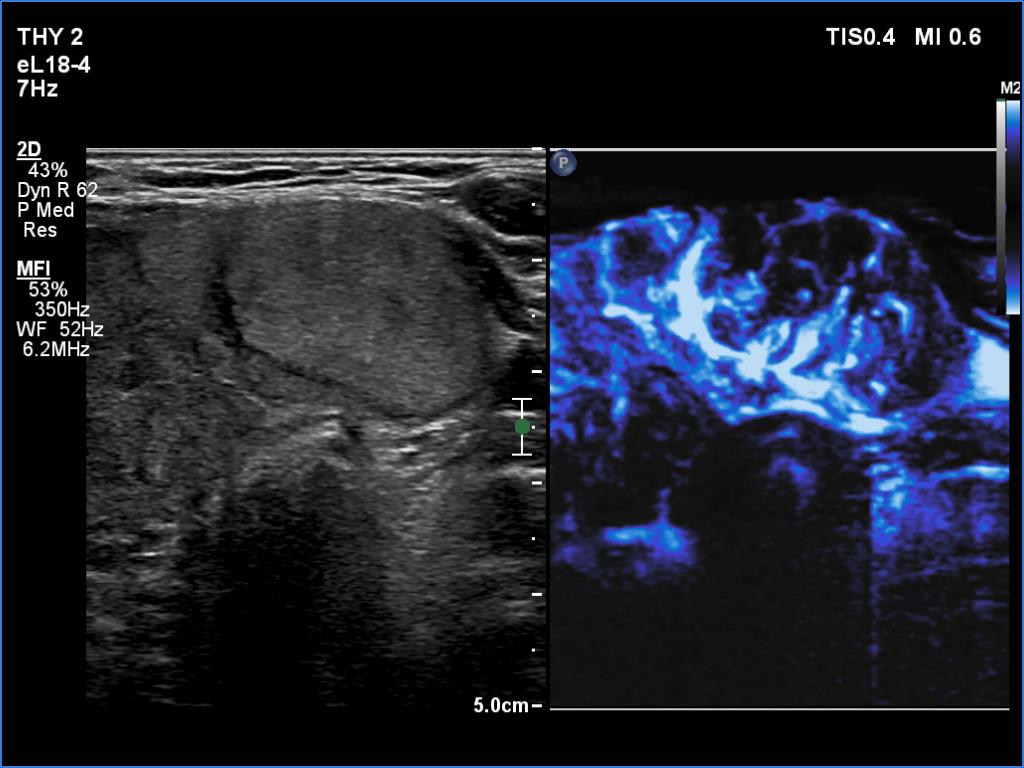

Lymphocytic thyroiditis - case 609

Follow-up investigation 6 years after the first visit (ultrasonographic picture 9)

Right lobe, longitudinal scan

Isthmus, transverse scan, microflow imaging.